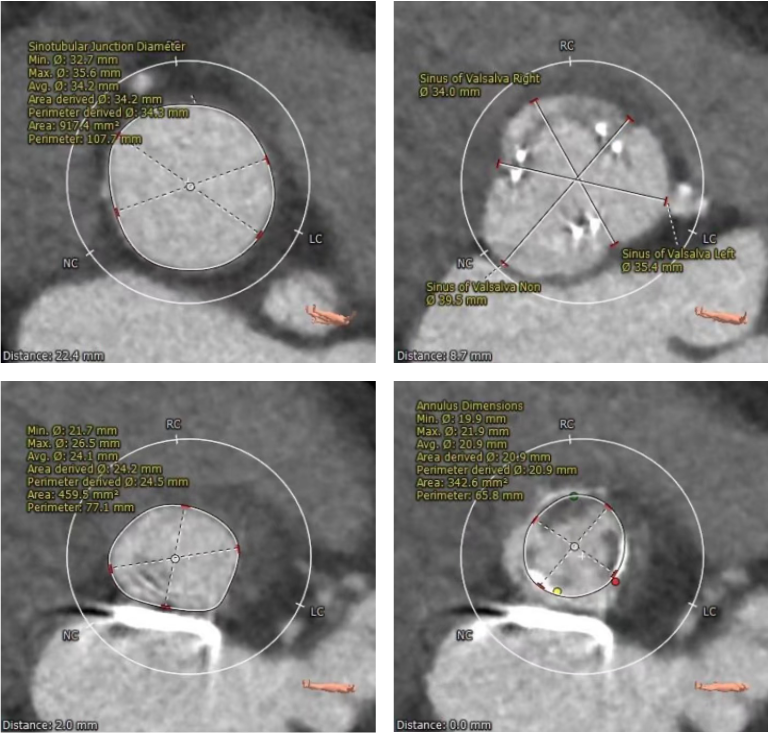

术前CT检查

主动脉根部评估

术前CT:三窦氏主动脉瓣,主动脉瓣SAVR术后,SMVP术后,二尖瓣人工瓣环距主动脉瓣环约5mm;瓦式窦内径尚可,窦管交界、升主动脉内径可。

左心室解剖评估

左心室心腔稍偏小,可能会出现急性大量主动脉瓣反流而导致低血压甚至循环崩溃的风险。

入路评估

外周入路血管散在钙化,双侧入路血管管径良好,整体入路血管条件尚可。